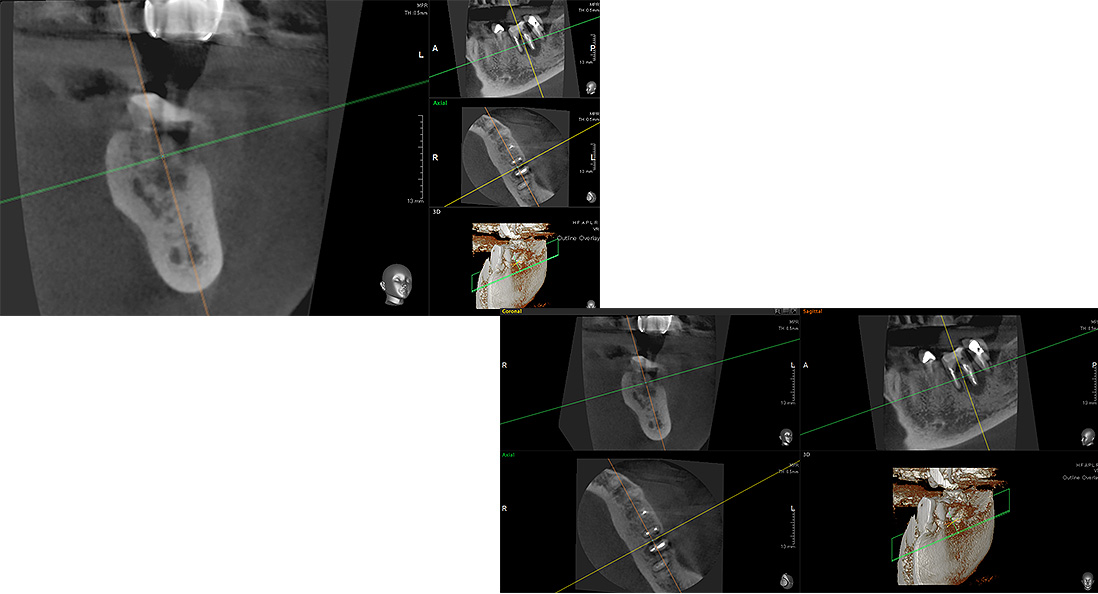

歯周組織再生療法は歯を支えている歯周組織(歯肉・セメント質・歯根膜・歯槽骨)を再生させる治療法です。

歯周外科手術では歯肉を切開して剥離することで、歯や骨が明確にみえる状態で徹底したバイオフィルムの除去が行われますが、この際に歯周組織再生材料を併用・応用することで失われた歯周組織の再生を促す処置が歯周組織再生療法です。